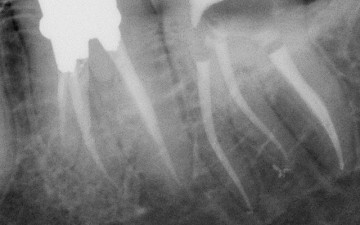

2/3 Postoperative x-ray Glide path with One G, Preflaring with One flare, Shaping with One curve in three waves up to the apex.